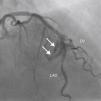

A 69-year-old man was referred for PCI of a 90% calcified lesion in the mid left anterior descending artery (LAD) involving the second diagonal branch (D2; Figure 1, arrow). After the left coronary ostium was cannulated and crossed with two BMW® wires, one to the LAD and other to the D2, predilation with a 2.5 mm×15mm Trek® balloon was performed and an unsuccessful attempt was made to cross the stenosis with a 2.75 mm×22mm Resolute Integrity® drug-eluting stent. Predilation was repeated with a 2.75 mm×15mm Trek® non-compliant balloon at high pressure. Suddenly, balloon rupture was detected and the angiogram showed LAD rupture with extensive contrast extravasation into the pericardium (Figure 2, arrows; Video 1). Protamine sulfate was used to reverse the effect of heparin and the drug-eluting stent was deployed with balloon inflation for 10minutes to seal the type III perforation but, as dye extrava- sation persisted, a 3.0 mm×19mm GraftMaster® covered stent was superimposed, followed by rapid cessation of contrast leakage (Video 2). The D2 branch was lost (Figure 3, arrows), and periprocedural myocardial infarction occurred. The final image showed pericardial effusion (Figure 4; Video 3). The echocardiogram excluded tamponade. Forty-eight hours later, atrial fibrillation occurred with hemodynamic deterioration. Pericardiocentesis was performed and 50ml of serosanguineous fluid was drained. Sinus rhythm was restored, with favorable evolution thereafter.